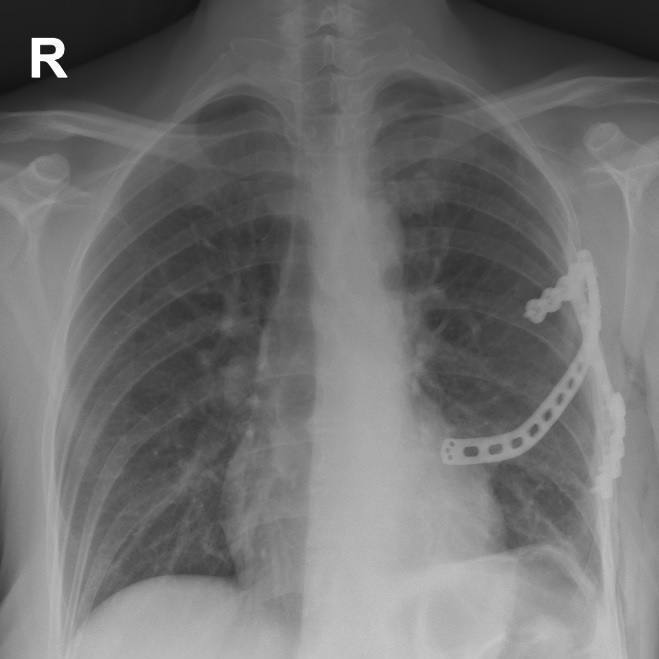

В ходе операции междисциплинарная команда в составе торакального хирурга Алексея Паршина и травматолога-ортопеда Ярослава Рукина установила имплант размером 12 см через разрез всего 5 см.

«Для лучшего заживления надкостница с ребер была частично удалена, выполнена туннелизация в грудной мышце. Макет импланта был установлен в подготовленное ложе и намечены точки фиксации. После титановый протез был установлен и зафиксирован специальными винтами. Рану послойно ушили с применением безузлового внутрикожного косметического шва», — добавил Алексей Паршин.

Послеоперационный период протекал без осложнений. У пациентки сохранена полная подвижность руки и дыхательная функция. Сейчас она выписана домой в удовлетворительном состоянии.